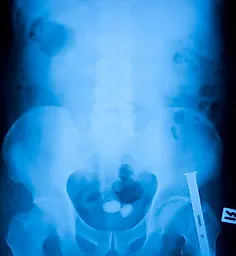

Большая часть камня удалена с помощью перкутанной ультразвуковой нефростолитотомии. Остаточные фрагменты, недостижимые для перкутанного доступа (отмечены стрелками), разрушают посредством экстракор-поральной ударно-волновой литотрипсии С. На контрольной обзорной урограмме остаточные фрагменты не определяются. D. На контрольной внутривенной урограмме выявляется прекрасный функциональный и анатомический результа